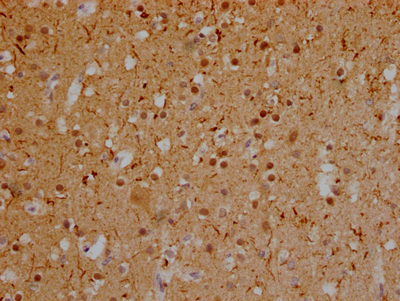

IHC image of CSB-RA246354A0HU diluted at 1:100 and staining in paraffin-embedded human glioma cancer performed on a Leica BondTM system. After dewaxing and hydration, antigen retrieval was mediated by high pressure in a citrate buffer (pH 6.0). Section was blocked with 10% normal goat serum 30min at RT. Then primary antibody (1% BSA) was incubated at 4℃ overnight. The primary is detected by a Goat anti-rabbit IgG polymer labeled by HRP and visualized using 0.05% DAB.

IHC image of CSB-RA246354A0HU diluted at 1:100 and staining in paraffin-embedded human brain tissue performed on a Leica BondTM system. After dewaxing and hydration, antigen retrieval was mediated by high pressure in a citrate buffer (pH 6.0). Section was blocked with 10% normal goat serum 30min at RT. Then primary antibody (1% BSA) was incubated at 4℃ overnight. The primary is detected by a Goat anti-rabbit IgG polymer labeled by HRP and visualized using 0.05% DAB.